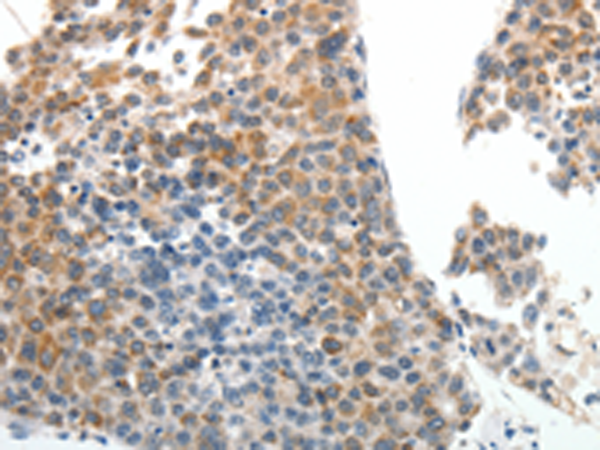

分类: 科研抗体货号: P04248别名: STSL应用: IHC反应种属: Human